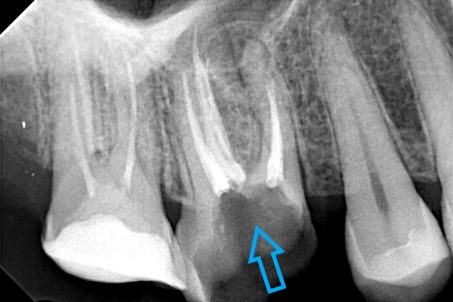

Ο ασθενής πονούσε πολύ στον άνω γομφίο, που είχε απονευρωθεί πριν από χρόνια. Αποφασίστηκε η επανάληψη απονεύρωσης του δοντιού, κατά την οποία διαπιστώθηκε οτι υπήρχε και τέταρτος ριζικός σωλήνας που δεν είχε βρεθεί και επεξεργαστεί κατά την πρώτη προσπάθεια απονεύρωσης. Πλέον το δόντι είναι ασυμπτωματικό.

Παλιά απονεύρωση του δύο άνω γομφίου

Νέα απονεύρωση στον άνω γομφίο